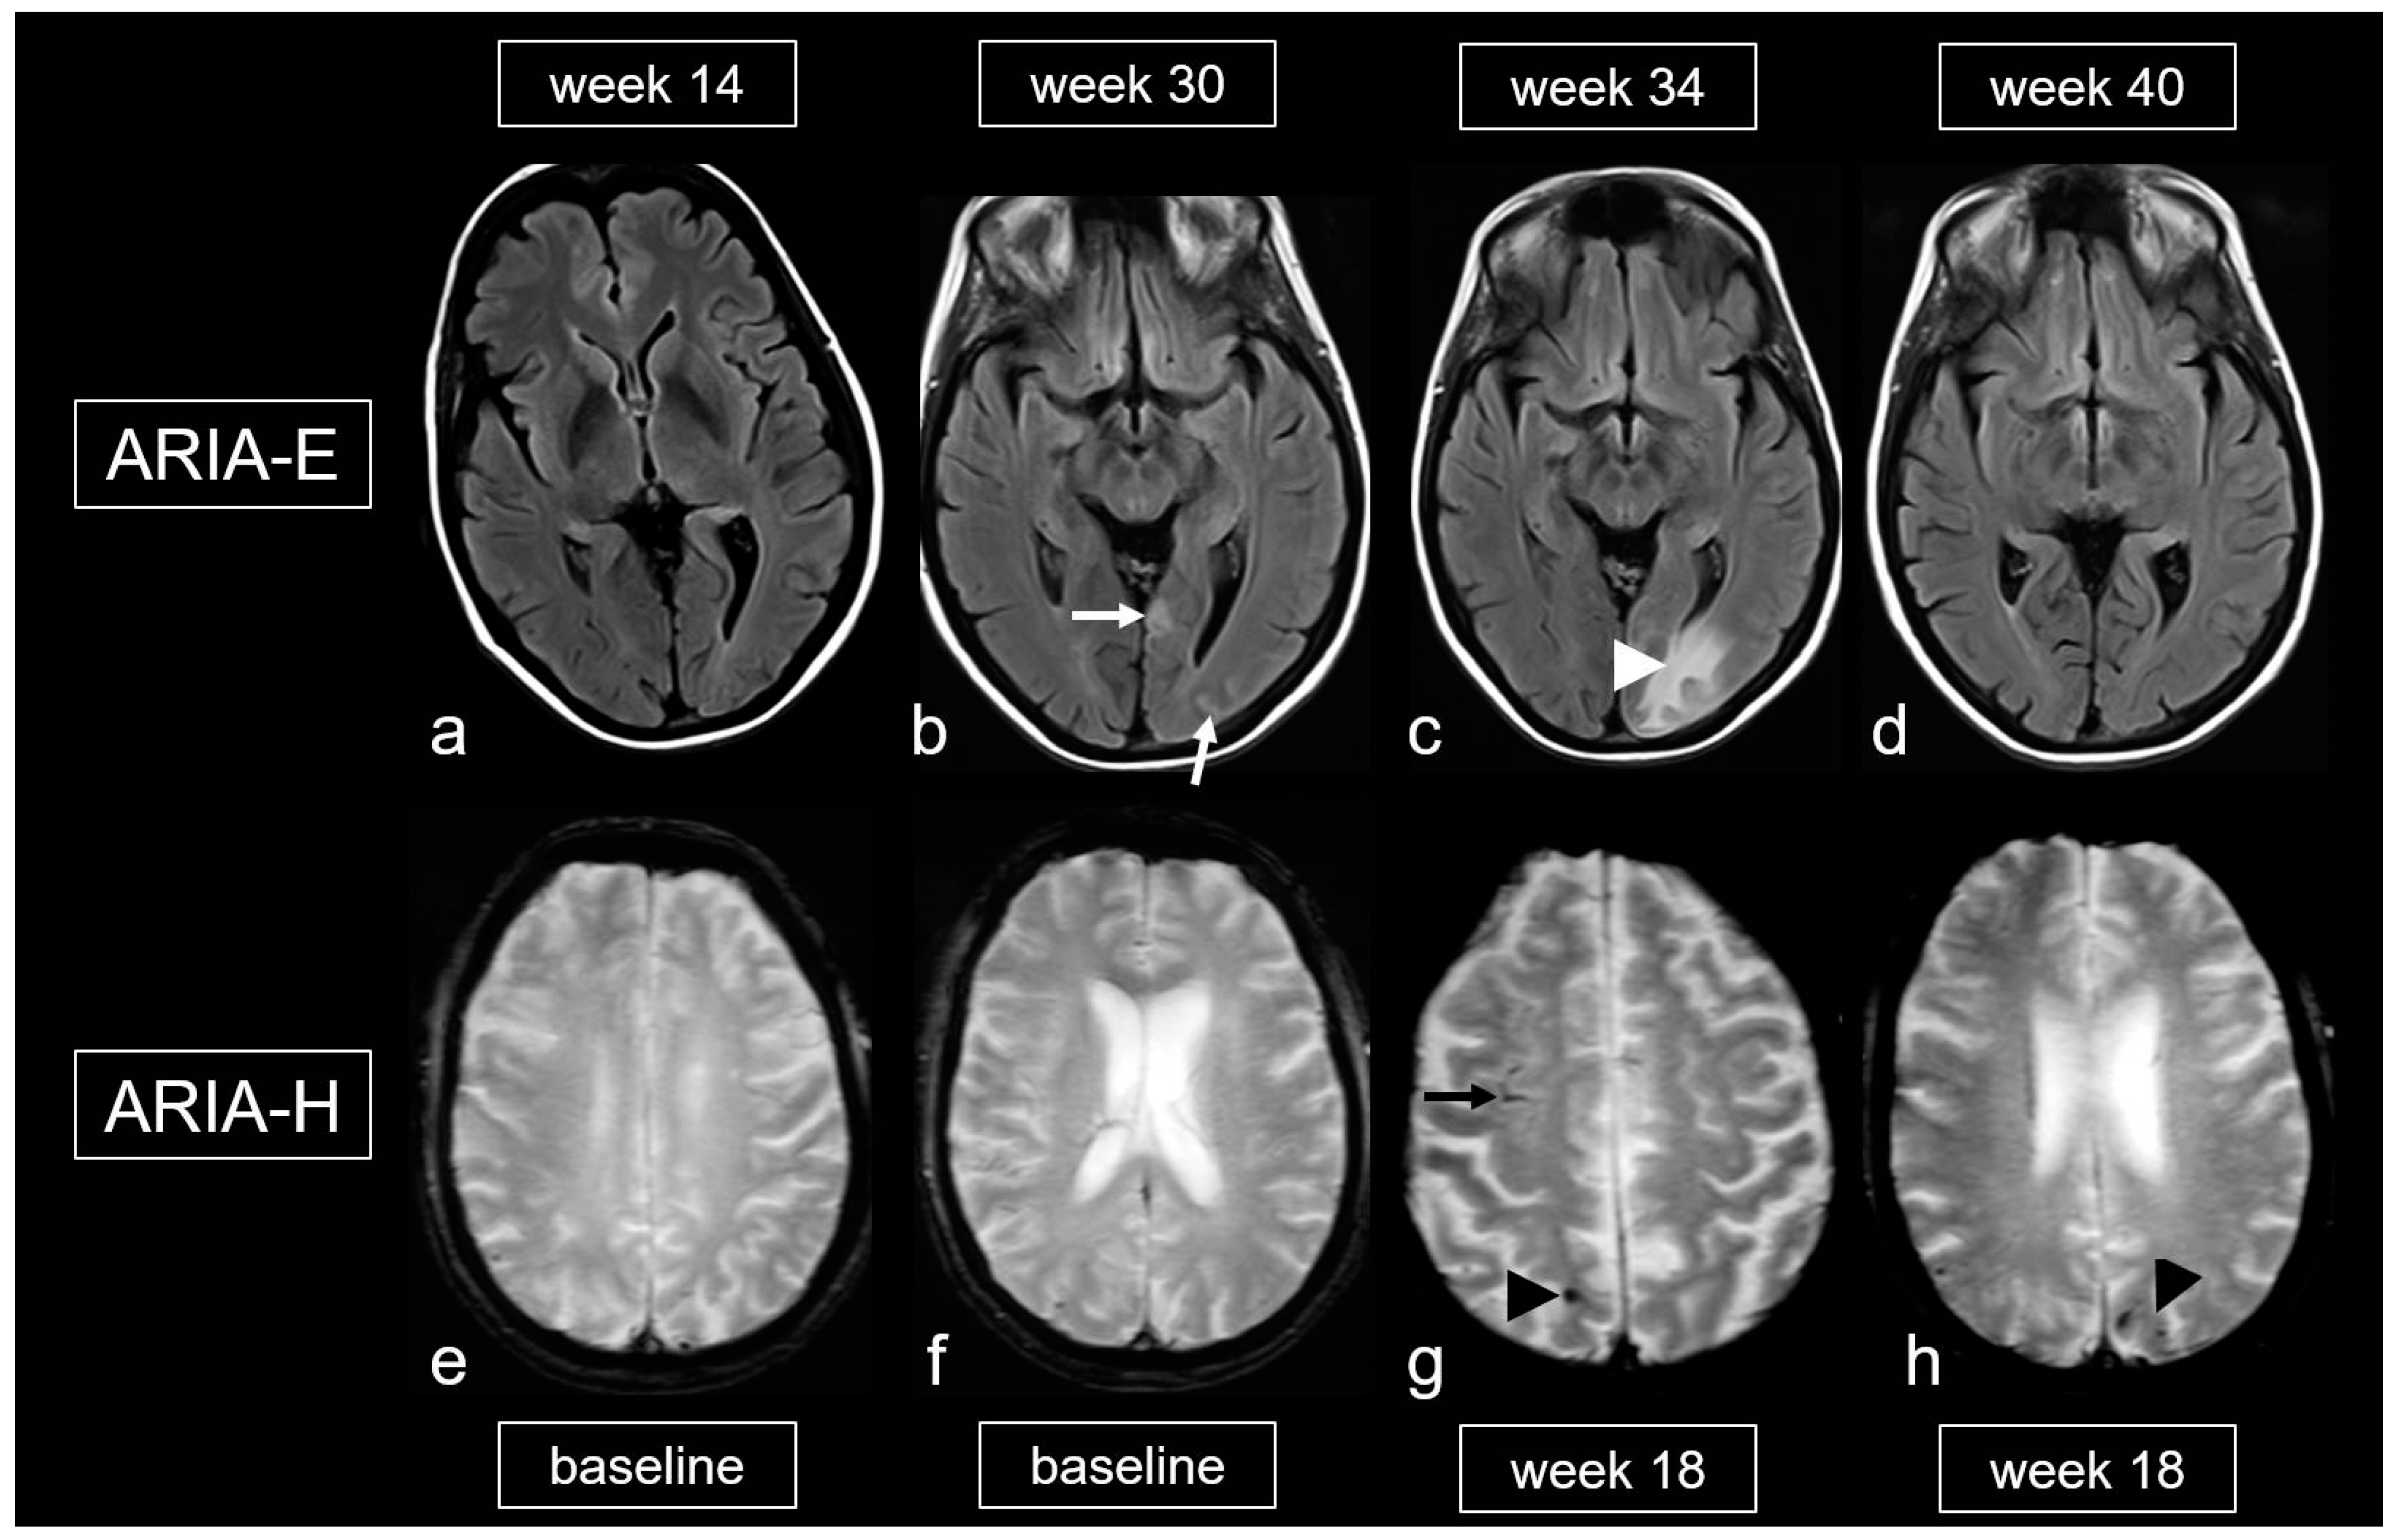

Figure 9.

Amyloid-related imaging abnormalities (ARIA). (a–d): Fluid-attenuated inversion recovery (FLAIR) images showing ARIA-E (edema, effusion) in a patient treated with aducanumab, week 14 (a), 30 (b), 34 (c) and 40 (d) after treatment initiation; sulcal effusions ((b), arrow) and edema in the occipital lobe ((c), arrowhead), completely decreased at week 40 (d). (e–h): T2*-weighted images (WI) demonstrating ARIA-H (hemorrhagic) in a 68-year-old woman treated with aducanumab, baseline (e,f) and week 18. (g,h): Cortical superficial siderosis (cSS; arrow) and microbleeds (MB; arrowhead); MRI 1.5T.

Biochemically, there is an increased conversion of the less water-soluble Aß-42, located in the parenchyma, into the more soluble Aß-40. This leads to a significantly higher concentration of Aß-40 in the perivascular drainage system, resulting in overload and potential damage to smooth muscle cells, among other effects [3,4,5,101,119,122]. This can cause extravasation of protein-rich fluid, leading to the development of edema and leptomeningeal effusions (ARIA-E). The extravasation of erythrocytes may result in ARIA-H (see Figure 9) [101,105].

Finally, the literature also mentions an iatrogenic variant of CAA-ri related to the frequent and dose-dependent occurrence of ARIA, which affects up to 41.3% [101,105,124,125]. The gradations of ARIA-E and ARIA-H are outlined in Table 5 and Table 6 [105,126]. It is important to note that, unlike spontaneous CAA-ri, only about 20% of patients with proven ARIA on MRI exhibit clinical symptoms, such as headache, confusion and other psychopathological abnormalities, visual disturbances, nausea and vomiting [101,105,124,125,126]. These symptoms typically arise within the first 3 months of treatment and are usually reversible.